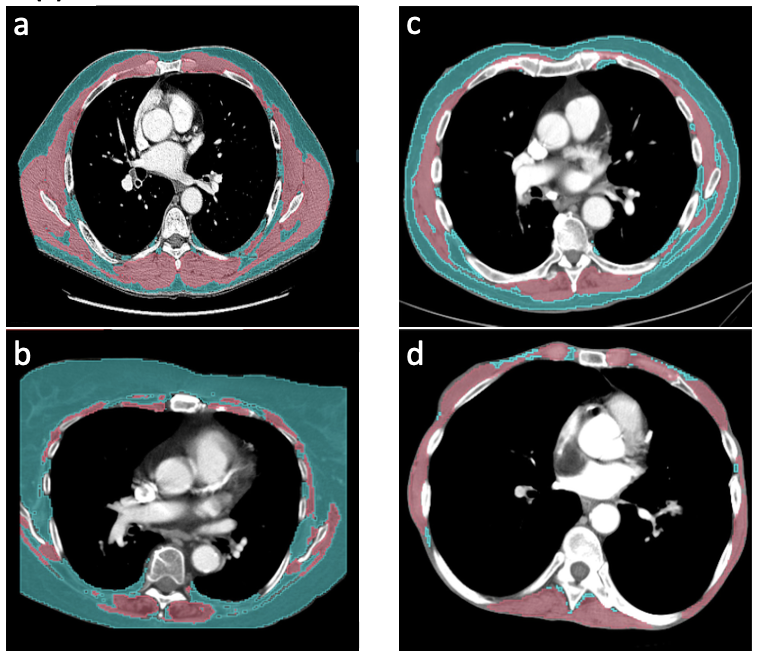

The study included 802 aNSCLC patients (415 female, 387 male) treated with first-line systemic therapy across 17 Canadian cancer centers, with baseline and follow-up CT scans available at 8 ± 4 weeks after treatment initiation. SMV and SFV were extracted from segmentation masks based on a 3D U-net architecture, and SMV-%CFB and SFV-%CFB were divided into quartiles, with Q4 representing the highest-risk group (greatest loss). Kaplan–Meier and Cox proportional hazards analyses assessed associations with median OS (mOS).